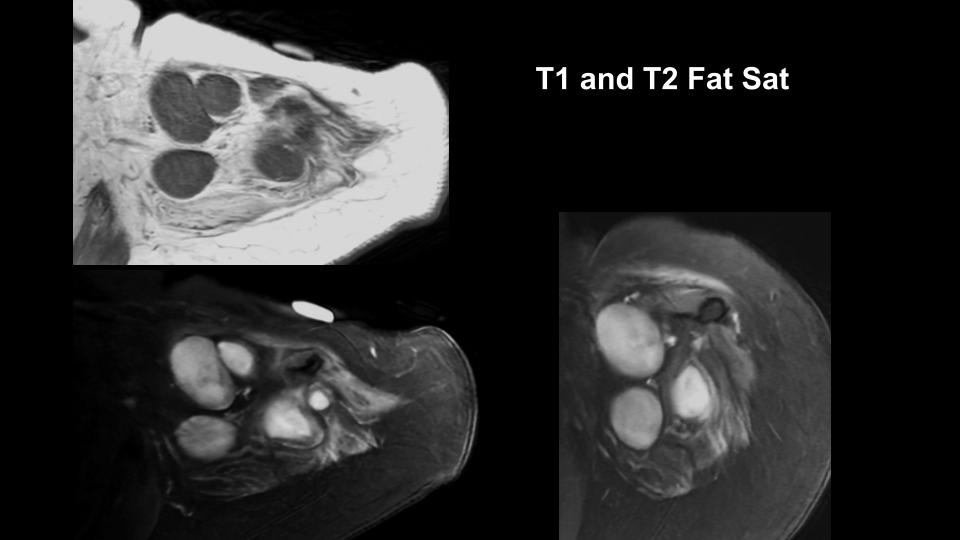

Figure 1 for case Stump neuromas

Figure 1

Figure 2 for case Stump neuromas

Figure 2